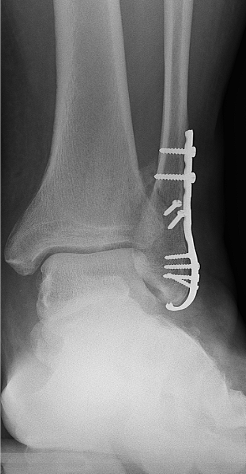

If the ankle fracture is more severe, or if the bones are displaced, i.e. not lined up correctly, surgery may be recommended to fix the fracture. This is called operative treatment. There are several different types of surgery that can be used to fix an ankle fracture, depending on the specific injury.

The most common type of surgery is called an open reduction and internal fixation (ORIF). Incisions are made through the skin to access the broken bone(s). Your surgeon will manually move the bone pieces back into place and hold them in place using special screws or plates. The skin is then closed with stitches. With this treatment, the bones are expected to heal in the proper position.

After surgery, the patient will need to wear a splint or special boot to keep the ankle stable while it heals. Putting weight on the leg may be restricted until up to 6 weeks after surgery. Physical therapy may also be recommended to help the person regain strength and mobility in the ankle.